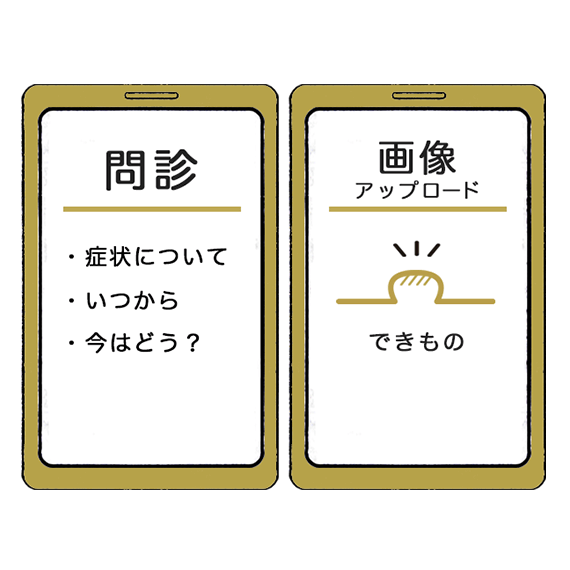

問診表に記入

(できもの診察は、

患部画像をアップロード) -